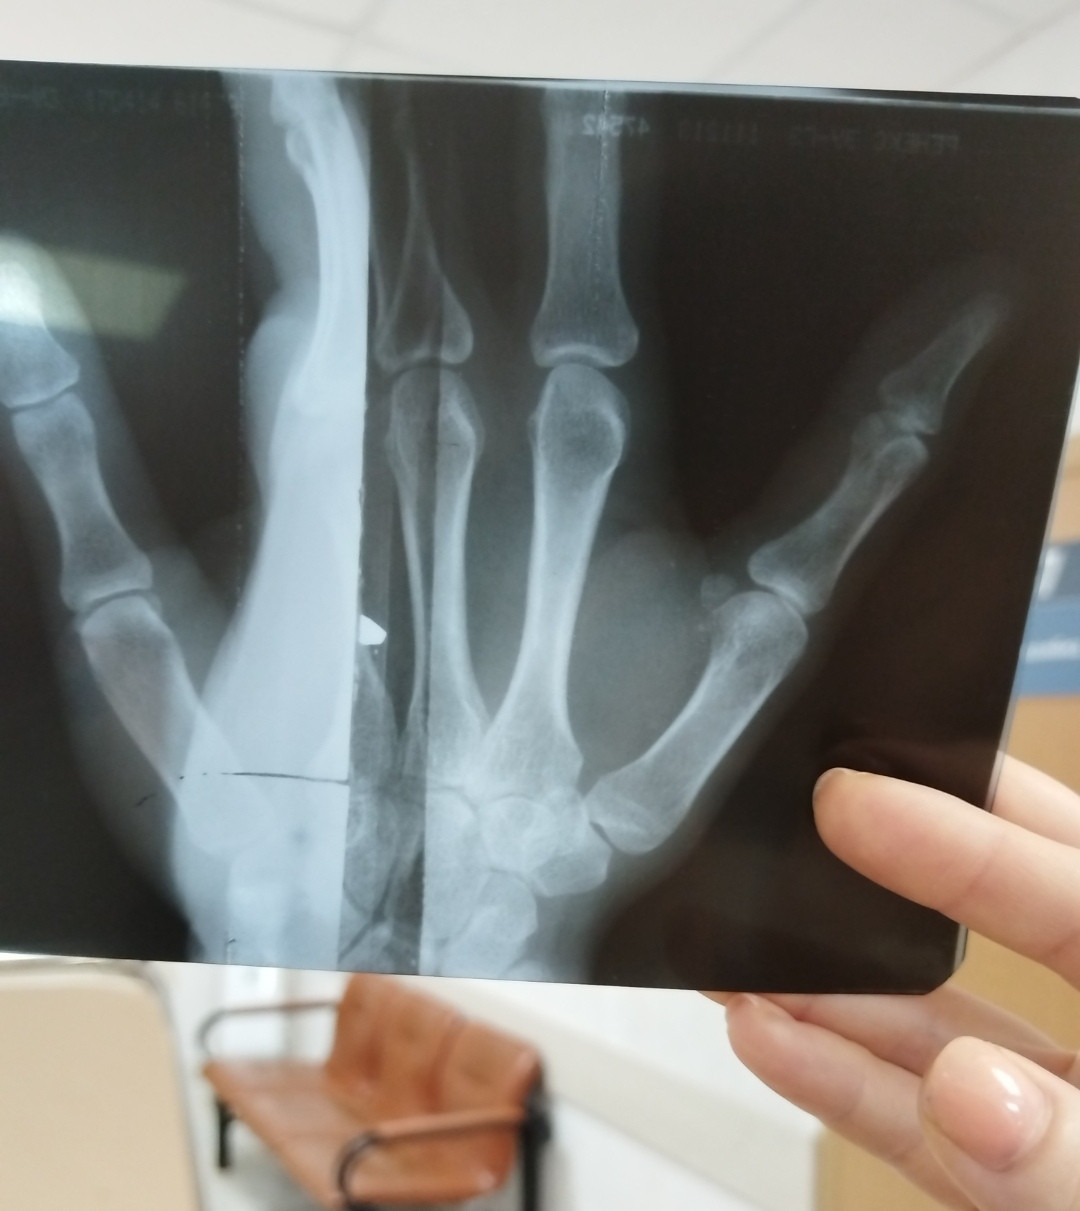

Был сильный удар большого пальца. Опух. Что можно сказать по снимку?

Здравствуйте. По вашему снимку заметна линия, похожая на перелом в области проксимальной фаланги большого пальца. Но качество изображения и угол могут давать искажения, поэтому окончательно подтвердить диагноз может только рентгенолог или травматолог при очном осмотре и официальном описании снимка. Рекомендую обязательно показать рентген врачу и  он сможет точно сказать, есть ли перелом и нужна ли фиксация.